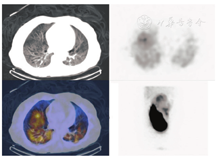

在所有患者中肝和肺之间均存在一定程度的血液分流,可能是正常分支血管、增生的肿瘤血管或动静脉畸形造成,称之为肺肝分流[26,27]。肺肝分流可在术前通过注射放射性标记的99Tcm-大颗粒聚合人血清合白蛋白(macroaggregated albumin, MAA)后计算得出一个肺内分流率的数据[28]。因99Tcm-MAA粒子的大小和分布与90Y微球相似,从而可预估对肺的潜在辐射损伤[29]。通过肝动脉导管注射多个小剂量的99Tcm-MAA(总剂量约0.148~0.185 GBq),使其分布在整个肝脏中[23,28,29]。采用腹部平面显像或SPECT(SPECT/CT)可获得术前成像(图2)[28]。计算肺内放射性示踪剂摄取的总计数,并将其除以肺和肝脏内计数的总和,从而得到肺内分流率(图3)。如果肺内分流率在单次给药剂量下大于25 Gy(树脂微球)或30 Gy(玻璃微球),或在肺中沉积的累积剂量大于50 Gy,则会对肺部造成辐射损伤风险,此时90Y微球选择性内放射治疗就属于禁忌证(图4)[30]。